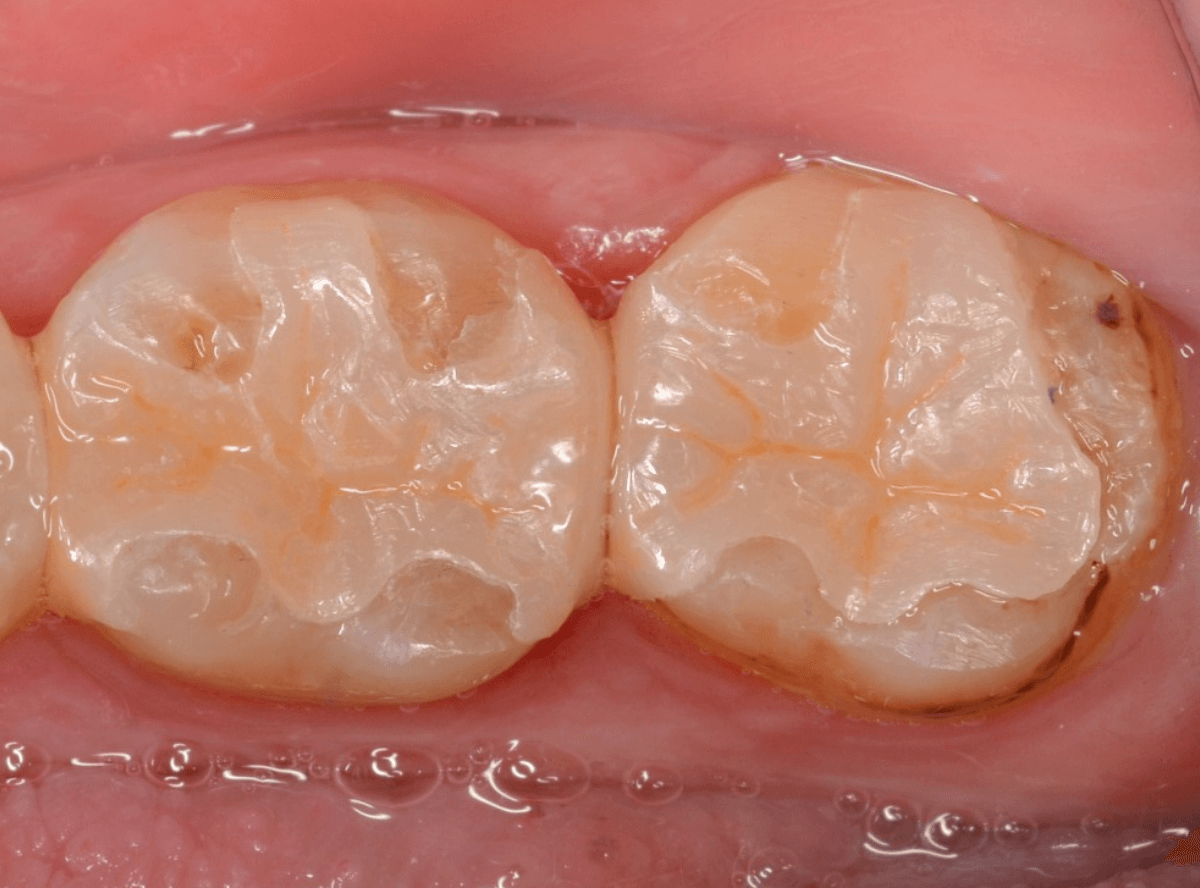

「下の奥歯の銀歯を白くしたい」というご希望の患者さんです。

メタル・インレーとメタル・クラウンが入っていますね。

set後の写真です。

患者さんにも満足していただける仕上がりになりました。

治療前後の写真になります。

やはり、印象が大きく変わりますね。